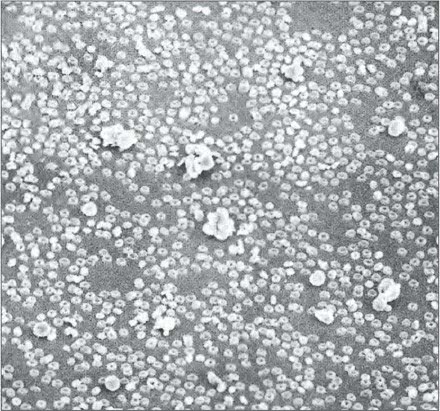

Макрофотография клеток крови человека. Клетки, напоминающие пончики, – это красные кровяные тельца (эритроциты), переносящие кислород. Более крупные комки – белые кровяные тельца, которые уничтожают чужеродные микроорганизмы.

Публикуется с разрешения Д. Голди, Калифорнийский университет, Лос-Анджелес

Электронные микрофотографии клеток крови человека (с последовательным увеличением). На верхнем снимке большинство клеток – красные кровяные тельца. Клетка, которая занимает весь нижний снимок, это B-лимфоцит, внутрь которого мы заглянем на следующей странице. Его диаметр – около одной десятитысячной сантиметра.